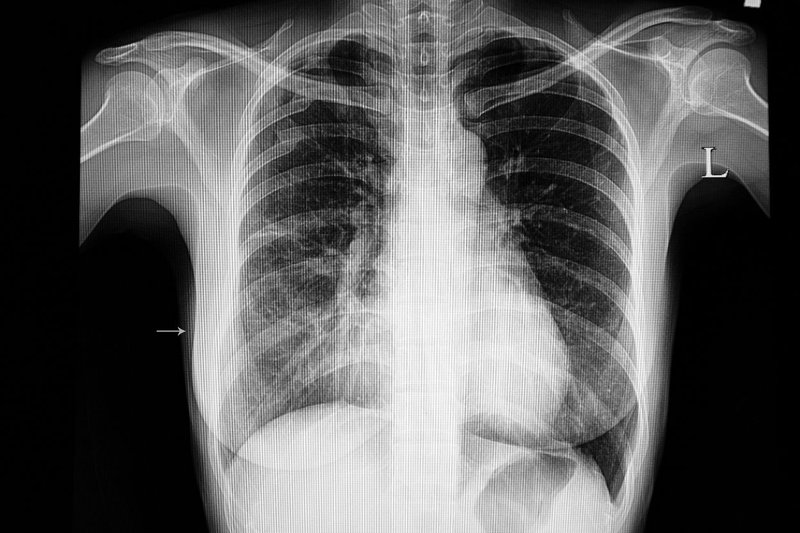

Each lung is filled with thousands of small airways that branch into tiny air sacs, which allow oxygen from the air we breathe to enter the blood. If you have pneumonia, these air sacs in the lung fill with fluid and mucus, which interferes with the breathing process.

Pneumonia is usually caused by an infection with bacteria or viruses that have been inhaled into the lungs. Your body’s immune system then sends white blood cells to attack the germs that are causing the infection. This causes the air sacs in the lung, called alveoli, to become filled with fluid and mucus, which can cause difficulty breathing.